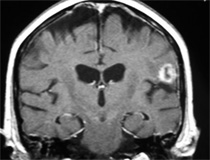

Después:

Control a 3 años post radiocirugía: En lugar del tumor se observa una mínima cicatriz. Los síntomas desaparecieron y el paciente retomó su vida profesional habitual